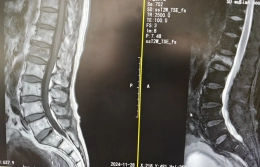

对普通人来说,平躺着好好睡一觉,是再简单不过的事情,但对小李(化名)来说却是一种奢求——16年前,他因患上强直性脊柱炎未及时治疗,身体逐渐前屈,最后脊柱后凸达到90度。他无法像正常人一样抬头挺胸,甚至...